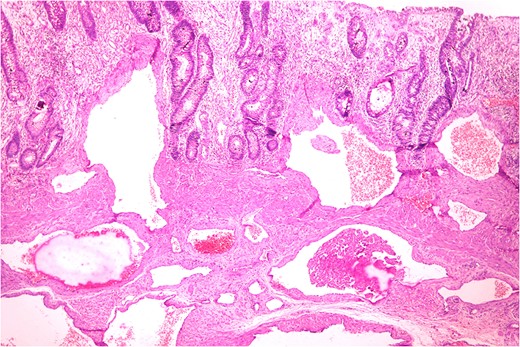

Anastomosing and dilated vascular channels in the submucosal area with congested and thrombosed blood vessels. (H&E ×400).

Histopathologically diagnosis of Cavernous Vascular Malformation—Diffuse infiltrating (expansive) type was given.